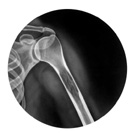

Röntgen

Oberarmknochen

Die beschädigten Bereiche stellen sich normalerweise als dunkle Flecken auf dem Röntgenfilm dar. Oft sind Knochenmetastasen jedoch nicht auf der Röntgenaufnahme sichtbar, wenn der Krebs nicht ungefähr die Hälfte des Knochengewebes in diesem Bereich zerstört hat.

Aufgrund eines Röntgenbildes ist es jedoch nicht möglich zu beurteilen, wie stark der Knochen in seiner tragenden Funktion und Stabilität beeinträchtigt ist.